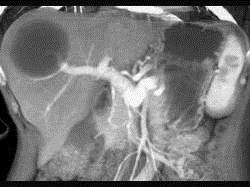

女性,45岁,偶有右上腹部胀痛,CT检查见图,最可能的诊断是 ( )A、肝血管瘤B、肝棘球蚴病C、肝囊肿D、肝脓肿E、肝癌

问题 女性,45岁,偶有右上腹部胀痛,CT检查见图,最可能的诊断是 ( )

选项 A、肝血管瘤 B、肝棘球蚴病 C、肝囊肿 D、肝脓肿 E、肝癌

答案 C